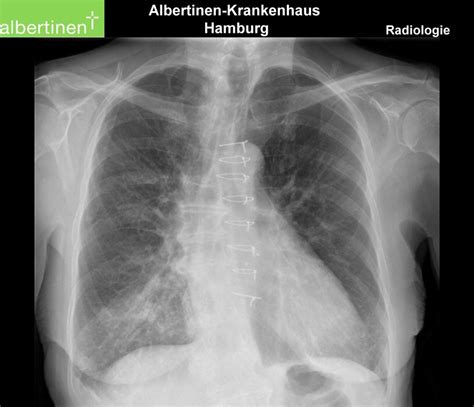

To a radiologist, a healthy lung appears mostly black on an X-ray because it is filled with air, which does not block X-ray beams. However, when pneumonia is present, the affected area of the lung becomes filled with inflammatory fluid and cells. This change in density causes the area to appear as white or grey patches, technically known as “opacities” or “infiltrates.”

• Consolidation: This refers to a solid white area where the air sacs are completely filled with fluid.

• Air Bronchograms: Sometimes, the larger airways remain filled with air, appearing as dark branching lines amidst the white consolidation.

While a physical examination—including listening to the lungs with a stethoscope for crackles or wheezing—is standard, a chest X-ray is considered the “gold standard” for confirming the diagnosis. Aside from identifying the presence of pneumonia, imaging serves several other vital functions:

• Determining Severity: It helps doctors see how much of the lung is involved, which dictates whether a patient can be treated at home or needs hospital admission.